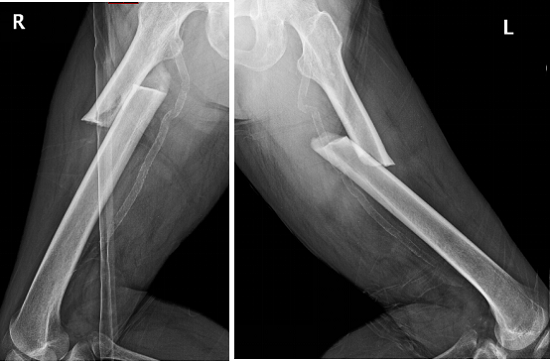

2018年上海交通大學醫學院附屬仁濟醫院創傷骨科碰到了一位從馬路臺階上摔倒的老年女性患者,拍片顯示是雙側股骨干近三分之一骨折(圖1),很對稱。

圖1

李占玉醫生團隊當時嚇了一跳,輕微暴力就能引起雙側股骨干骨折,這比較少見,肯定是病理性骨折,首先想到的是腫瘤所致,追問病史,患者否認有腫瘤病史,但有系統性紅斑狼瘡30多年,口服福善美5年,但已經停藥2年,在摔倒前有左側大腿根疼痛。根據病人的病史、體征和X線片所見,我們診斷為非典型股骨骨折,然后行髓內釘內固定術,術后8個月骨折愈合(圖2)。